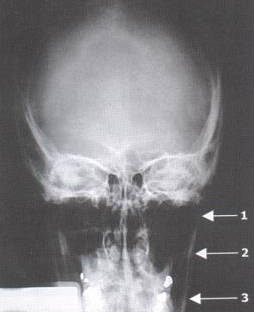

Standard Mandibular Series: Townes  View

Condylar